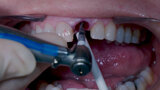

Fig. 11: Final implant position assessment.

Fig. 10: Implant placement with surgical handle.